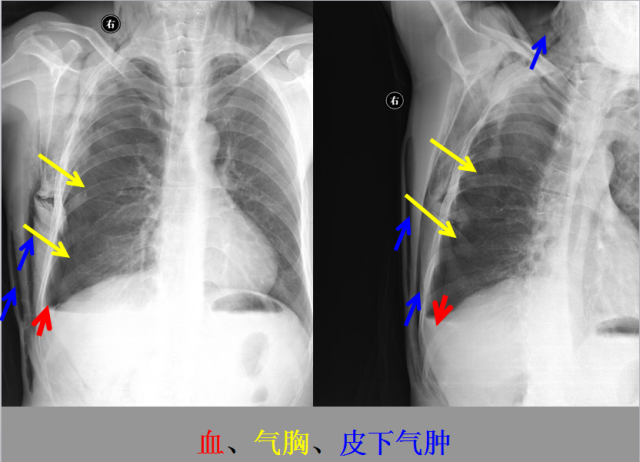

急胸症篇

04